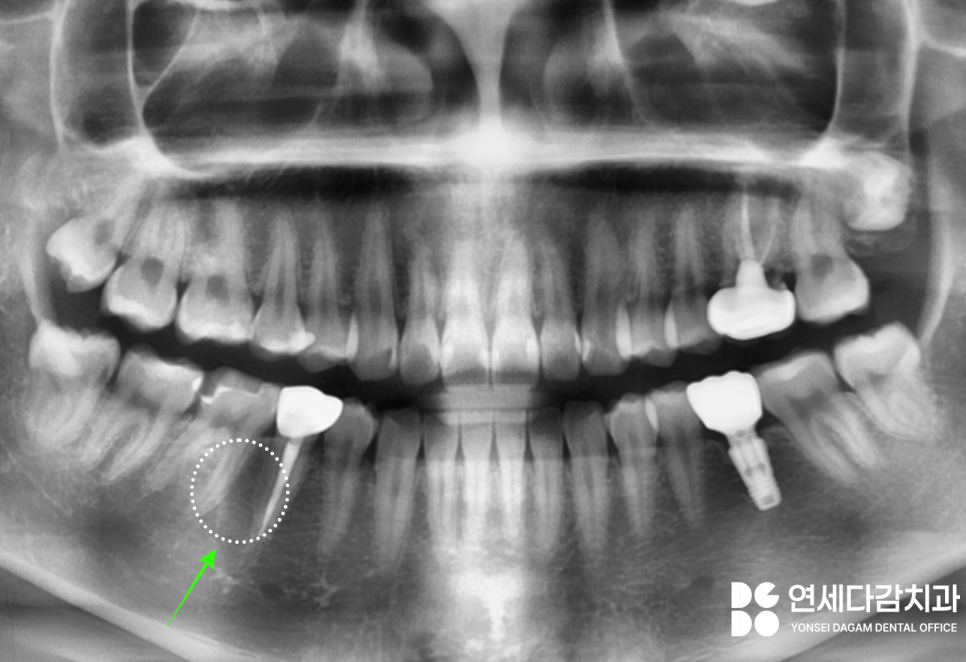

초진 엑스레이(2023.12.18)

오른쪽 아래 작은 어금니 부위에

매복 과잉치가 존재합니다.

(주로 파노라마에서 먼저 발견됩니다.)

특별한 증상은 없더라도

추후 낭종 발생, 인접치 치근 흡수 등

여러가지 위험 요소를 고려한다면

제거하는 것이 일반적입니다.